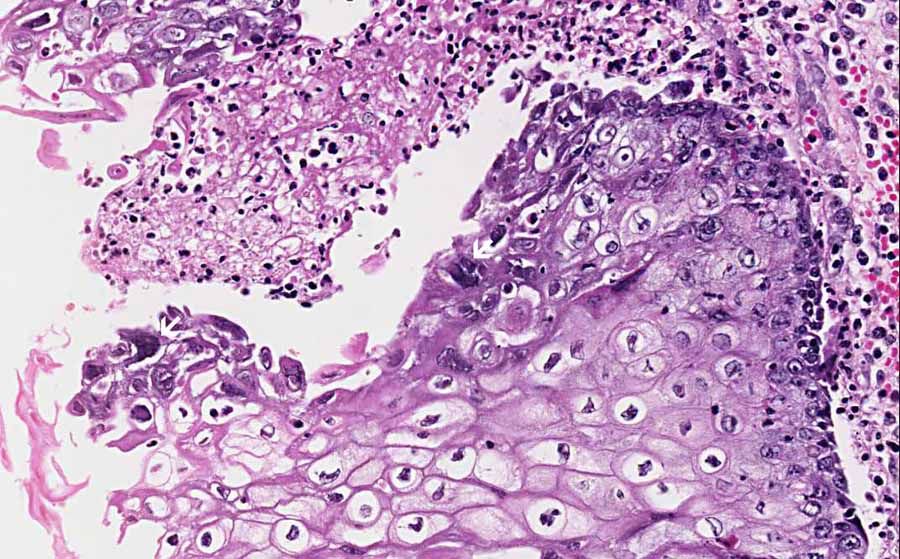

Esophageal infection occurs mainly in patients with impaired host defenses. 38 year old woman with esophagus ulcer; Infectious esophagitis (especially candida esophagitis) occasionally occurs in patients with diabetes mellitus or alcoholism, presumably because these diseases can impair immunity. Causes of esophagitis include stomach acids backing up into the esophagus, infection, oral medications and allergies. Evidenced based approach to the diagnosis and management of esophageal eosinophilia and eosinophilic esophagitis (eoe). Common forms of esophagitis include reflux esophagitis, infectious esophagitis, pill esophagitis candida esophagitis (see the image below) is the most common type of infectious esophagitis. Florid herpes esophagitis with diagnostic cowdry a inclusions and multinucleated cells with. Primary agents include candida albicans, herpes simplex virus, and cytomegalovirus.

Common forms of esophagitis include reflux esophagitis, infectious esophagitis, pill esophagitis candida esophagitis (see the image below) is the most common type of infectious esophagitis. Causes of esophagitis include stomach acids backing up into the esophagus, infection, oral medications and allergies. Herpes esophagitis is a viral infection of the esophagus caused by herpes simplex virus (hsv). „ odynophagia is the predominant presenting symptom. Therefore, hsv esophagitis was suspected, and valacyclovir was administered for 6 days. Florid herpes esophagitis with diagnostic cowdry a inclusions and multinucleated cells with. Esophagitis can cause painful, difficult swallowing and chest pain. Canalejo castrillero e, garcía durán f, cabello n, garcía martínez j.

Esophagitis due to herpes simplex virus (hsv) infection1,2. Epidemiology — herpes simplex virus (hsv) infection of the esophagus is usually observed in patients who are immunocompromised, but can occasionally be seen in patients who are. Herpes esophagitis is a viral infection of the esophagus caused by herpes simplex virus (hsv). Herpes esophagitis in healthy adults and adolescents: Canalejo castrillero e, garcía durán f, cabello n, garcía martínez j. 38 year old woman with esophagus ulcer; Common forms of esophagitis include reflux esophagitis, infectious esophagitis, pill esophagitis candida esophagitis (see the image below) is the most common type of infectious esophagitis. Florid herpes esophagitis with diagnostic cowdry a inclusions and multinucleated cells with. Eosinophilic esophagitis attributed to gastroesophageal re. Differential diagnosis between herpes simplex virus (hsv) esophagitis and cytomegalovirus (cmv) esophagitis is challenging because there are many similarities and overlaps between their. Causes of esophagitis include stomach acids backing up into the esophagus, infection, oral medications and allergies. Esophagitis can cause painful, difficult swallowing and chest pain. Herpes esophagitis is a viral infection of the esophagus caused by herpes simplex virus (hsv).